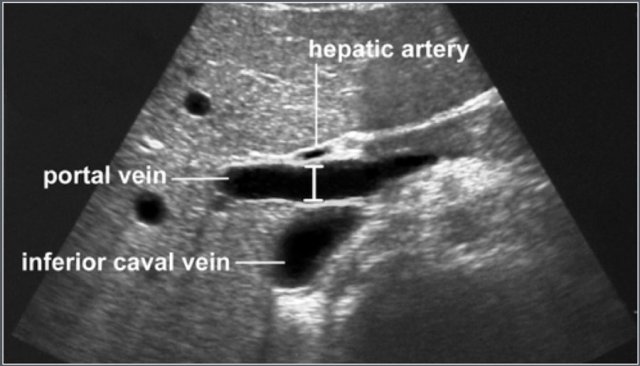

Measurement of portal vein diameter Measurement of portal vein diameter

The portal vein is visualized in the longitudinal axis from the splenomesenteric junction to the liver hilum.

The greatest anteroposterior diameter is measured at the site where the hepatic artery crosses the portal vein.